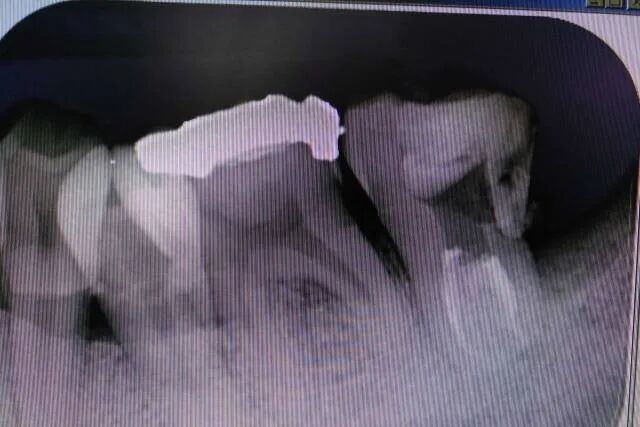

根管充填时,因根尖1/3常膨大,故建议根尖区采用侧方加压充填术或生物陶瓷类根管封闭剂+单尖充填法,上段采用热牙胶垂直加压充填技术来实现无空隙三维严密封闭。这个仅作建议,正常方法也可以。

图10 47根充片